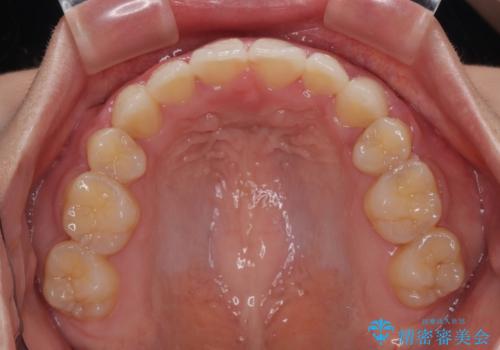

口元の突出感が改善されてことで、下唇に引っかかっていた上顎前歯も気にならなくなりました。

上下左右第一小臼歯4本を抜歯し、ワイヤー装置にて口元を引っ込めるよう矯正治療を行うこととしました。